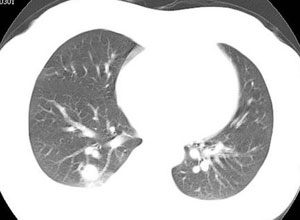

女性,30岁。

病史为胸痛20多天,无畏寒发热,无消瘦,无咳嗽咳痰。总之症状很逍遥。

临床以胸痛待查收住入院。

双肺野可见散在大小不等结节及肿块影,内密度不均匀,边缘部分清,部分欠清,纵隔未见明显肿大淋巴结.右侧胸腔少理积液.结合临床,考虑韦格肉芽肿可能吧,巨淋巴增生,结节病,特殊感染都要考虑.转移瘤临床不象.

多发、内可见含气支气管征,边界不清;纵隔内未内见明显肿大淋巴结。右侧少量胸腔积液。

考虑:1、化脓性肺炎?

2、肺霉菌感染?

本病例特点如下:

1.青年女性,以胸痛20多天就诊,无呼吸道及感染临床症状体征,无原发肿瘤病史;

2.肺ct表现为两肺多发大小不等结节影,大结节位于肺尖部,小结节多位于肺外带胸膜下,大结节内可见支气管充气征,周围可见月晕征(指在结节状或肉芽肿样病灶周围呈环形磨玻璃影),右肺门及腔静脉后可见小淋巴结,右侧胸腔内少量液体。

两肺散在分布大小不等的肿块及结节影,边缘毛糙,有分叶、毛刺,病灶密度不均匀,可见支气管充气相与空泡征。病变大多位于胸膜下,可见胸膜凹陷及胸腔积液。气管腔静脉间可见小结节影。